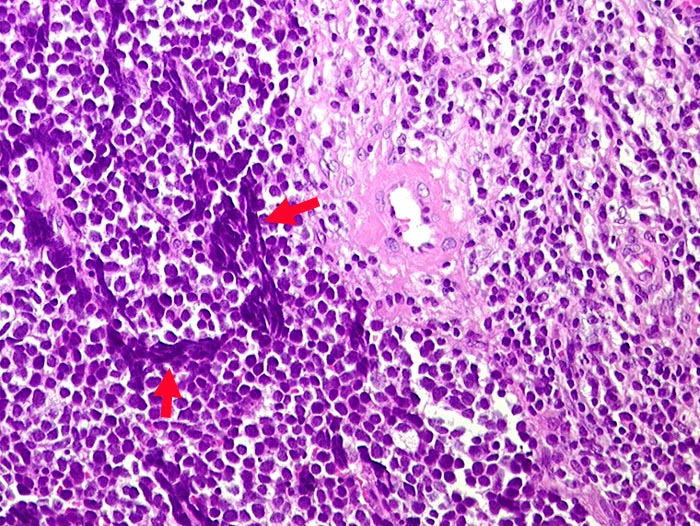

Metastase kleinzelliges Karzinom

Lymphknoten, mediastinal

Rechts im Bild Reste des Lymphknotengewebes mit einem bunten Gemisch verschiedenartiger Zellen. Links im Bild die im Vergleich mit Lymphozyten wenig grösseren nacktkernigen Tumorzellen mit typischen Quetschartefakten.

Vergrösserte Lymphknoten supraklavikulär rechts, thorakal und mediastinal. Unbekannter Primärtumor.